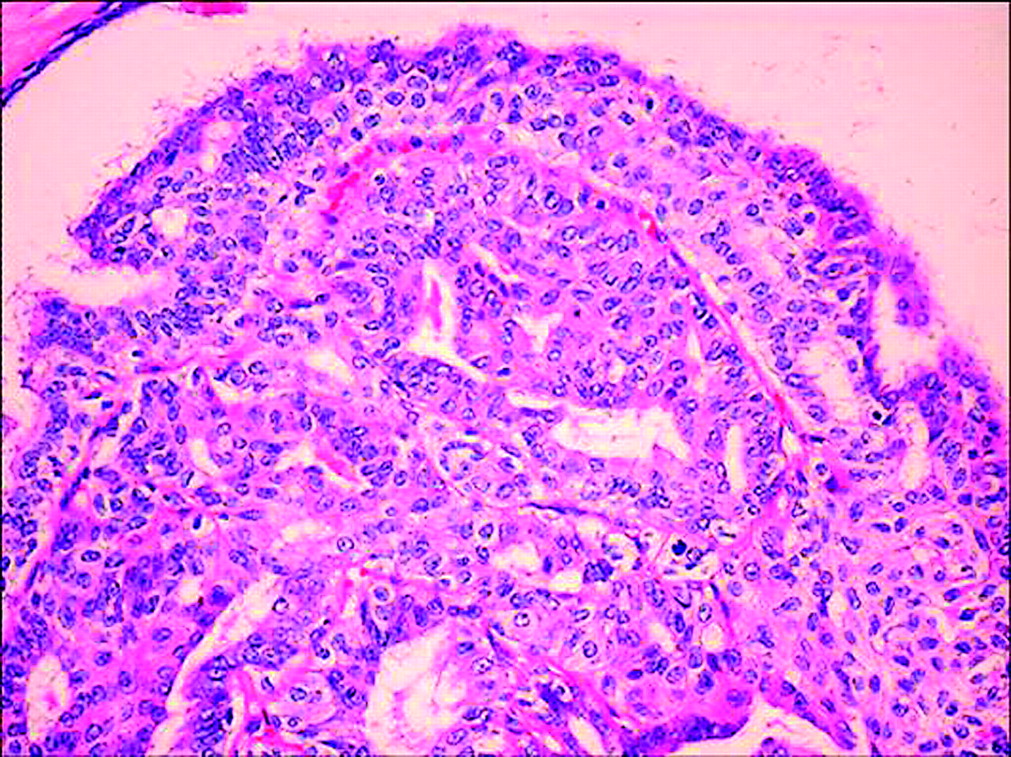

Malignant Adenomyoepithelioma Breast . Adenomyoepithelioma (ame) of the breast is a very rare tumor and is generally considered to be benign. Benign to low grade malignant behavior and a propensity for recurrence. Malignant adenomyoepithelioma (mame) of the breast is an extremely rare breast malignancy, in which they. Adenomyoepithelioma of the breast is an uncommon tumor characterized by dual differentiation into luminal cells and myoepithelial cells. Adenomyoepithelioma (ame) of the breast is a very rare tumor and is generally considered to be benign. Biphasic tumor with epithelial and myoepithelial components. Adenomyoepithelioma (ame) of the breast is a rare disease characterized by a bicellular pattern consisting of both ductal and myoepithelial cells [1, 2].

Pathology Outlines Adenomyoepithelioma & malignant adenomyoepithelioma Malignant Adenomyoepithelioma Breast Biphasic tumor with epithelial and myoepithelial components. Adenomyoepithelioma (ame) of the breast is a rare disease characterized by a bicellular pattern consisting of both ductal and myoepithelial cells [1, 2]. Adenomyoepithelioma (ame) of the breast is a very rare tumor and is generally considered to be benign. Adenomyoepithelioma (ame) of the breast is a very rare tumor and is generally. Malignant Adenomyoepithelioma Breast.